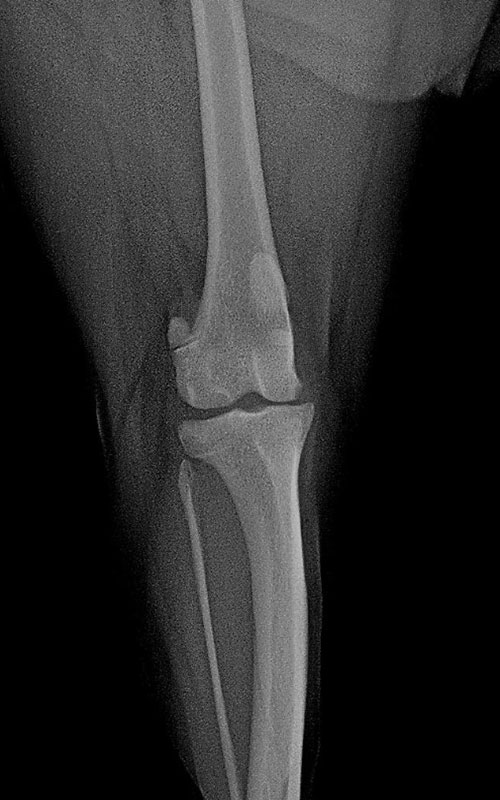

TPLO-M 2.4 with Smartvet polyaxial symmetrical TPLO plate (R15)

We also often encounter the co-application of MPL and CrCLR in mini dogs. In order to solve both problems within one operation, we used the modified TPLO technique published in 2019 (VCOT Vol.32 / 1). Members 2.0 and 2.4 of the symmetric “scream” TPLO plate family were modified to stabilize not only tibia plateau rotation but also tuberositas tibiae displacement. The completed prototypes are tested, the results are very encouraging. The additional techniques needed to solve MPL were used also (as needed: deepening of the patella groove, lateral tightening of the joint capsule, medial loosening).

2.0 buttress symmetrical TPLO plate:

not locking, can be used with 2.0 and 1.5 mm screws, the terrace (shift) is 2.3mm (for 2.5-6 kg dogs). There are no weak points here, the previously used plates may have broken in the neck due to bending and bending plate.

2.4 polyaxial butress symmetrical TPLO plate:

can be used with locking, polyaxial 2.4 torx head screws, the shift is 2.5mm. (for 5-12 kg dogs). In both cases, the insertion direction of the screws can be changed (polyaxiality !!!) to avoid the scew insertion into the joint.